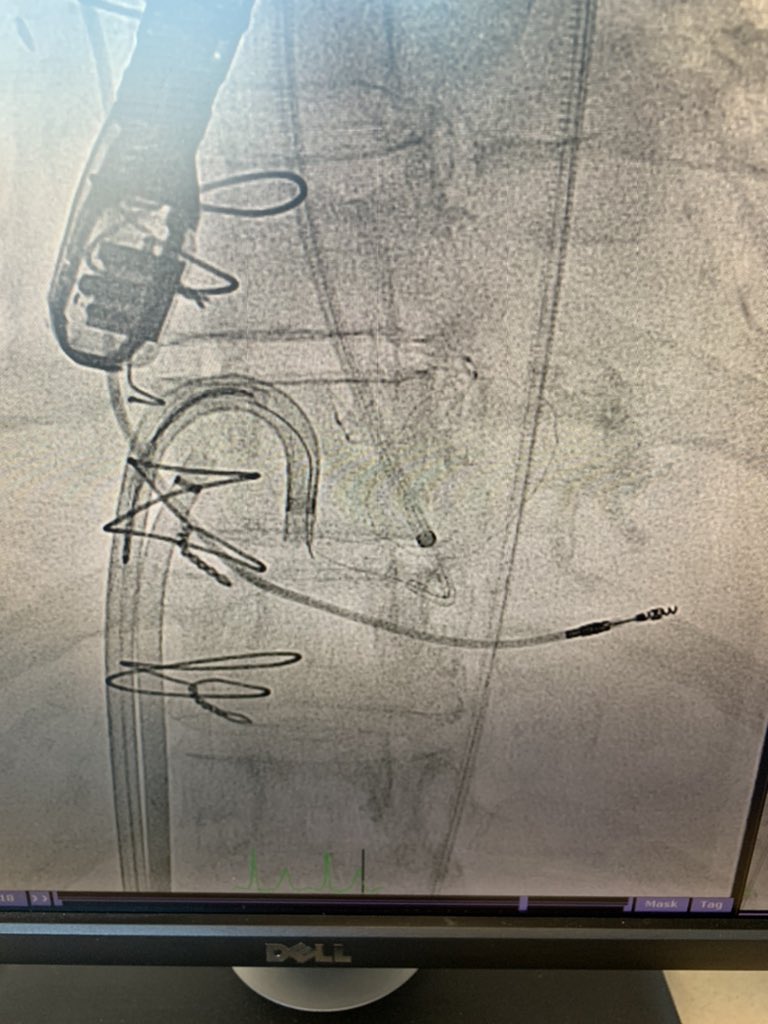

unable to cross medial PVL from LA. Surprisingly easy to cross from LV with.014 wire snared in LA.